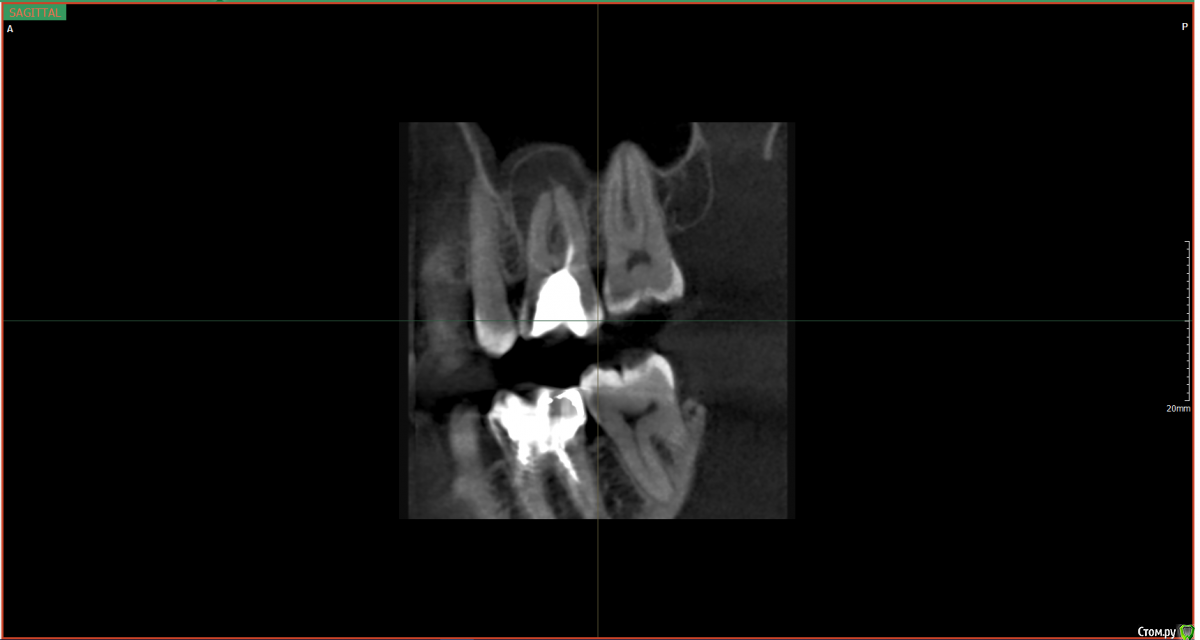

AlR Опубликовано 8 сентября, 2017 Автор Поделиться Опубликовано 8 сентября, 2017 (изменено) Вот образ диска, что дали когда делал снимок повторно пару часов назад https://yadi.sk/d/R7VKk0173MichUну и два скрина от туда Зуб сверху слева второй. Говорит удалять, шанс вылечить не больше 25%. Вроде как киста, так сложно лечится что ли? нифига не болит, постучал по зубам, как то все одинаково было) нигде не гремит Можно как то её победить не удалая зуб, а то бюджет на имплат пока что не запланирован Может это свищь? Очень похоже было на одну из фоток тут. Еще вспомнил, до этого зуб как бы чесался и как бы хотел наружу вылезти, не знаю как описать это ощущение. Фото самого сделать не могу, но на десне совсем маленький прыщик такой под цвет десны. Изменено 8 сентября, 2017 пользователем AlR Ссылка на комментарий

red_butler Опубликовано 8 сентября, 2017 Поделиться Опубликовано 8 сентября, 2017 Это периодонтит, требуется повторное лечение корневых каналов. Ссылка на комментарий

red_butler Опубликовано 8 сентября, 2017 Поделиться Опубликовано 8 сентября, 2017 Если судить только по снимку, то зуб удалять не нужно. Ссылка на комментарий